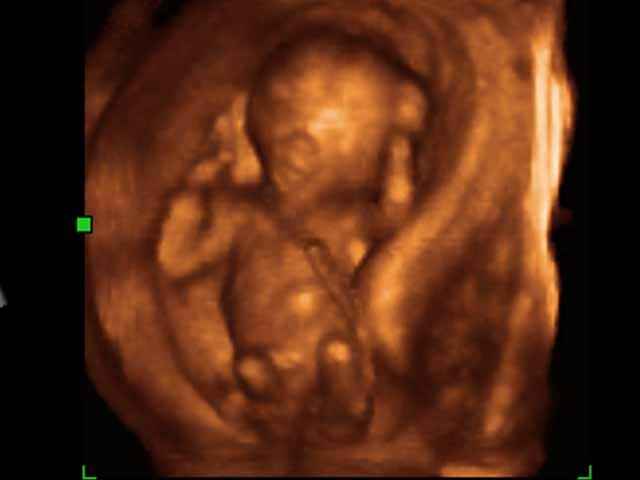

You can count there is a limb here, I can see feet and hands, I can see skull fragments, I can see trunk.

Dr. Gerson Weiss, abortionist, in sworn testimony in National Abortion Federation, et. al. v. Ashcroft, U.S. District Court, Southern District of New York, April 7, 2004